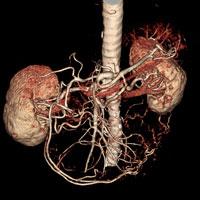

The first award exhibit, was entitled, A Truly Clientless AJAX-based 3D Image Viewer for MIRC Based on an IHE-TCE-Compliant 3D Client-Server Solution. This winning exhibit featured the AquariusWEB viewer, which was embedded seamlessly into the RSNA Medical Imaging Resource Center (MIRC) project for managing image-based teaching files for educational and research purposes.

The second award exhibit was entitled, Novel Uses of the Nintendo Wii Remote in the Navigation of Multidetector CT Datasets. In this instance, the Wii-mote was used as an alternative to traditional mouse-based input, to manipulate and review volumetric CT data. The flexibility of holding the Wii-mote in the hand removes the structured boundaries of a normal mouse and allows the user to remove the learning curve sometimes needed to manipulate a PC mouse.

Another exhibit utilized a “Multi-Touch” display to navigate volumetric CT and MR datasets. This technology allows users to manipulate data directly with their fingers through a touch screen and promises to remove the learning curve and constraints of a traditional mouse or trackball, icons and pull down menus.